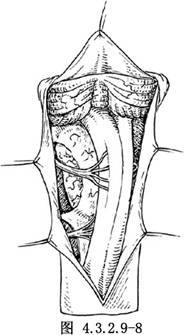

枕骨大孔區神經纖維瘤按其部位可位於延髓或脊髓的側方或前外側。手術切除的方法與該部位腦膜瘤切除術基本相同(圖4.3.2.9-8)。